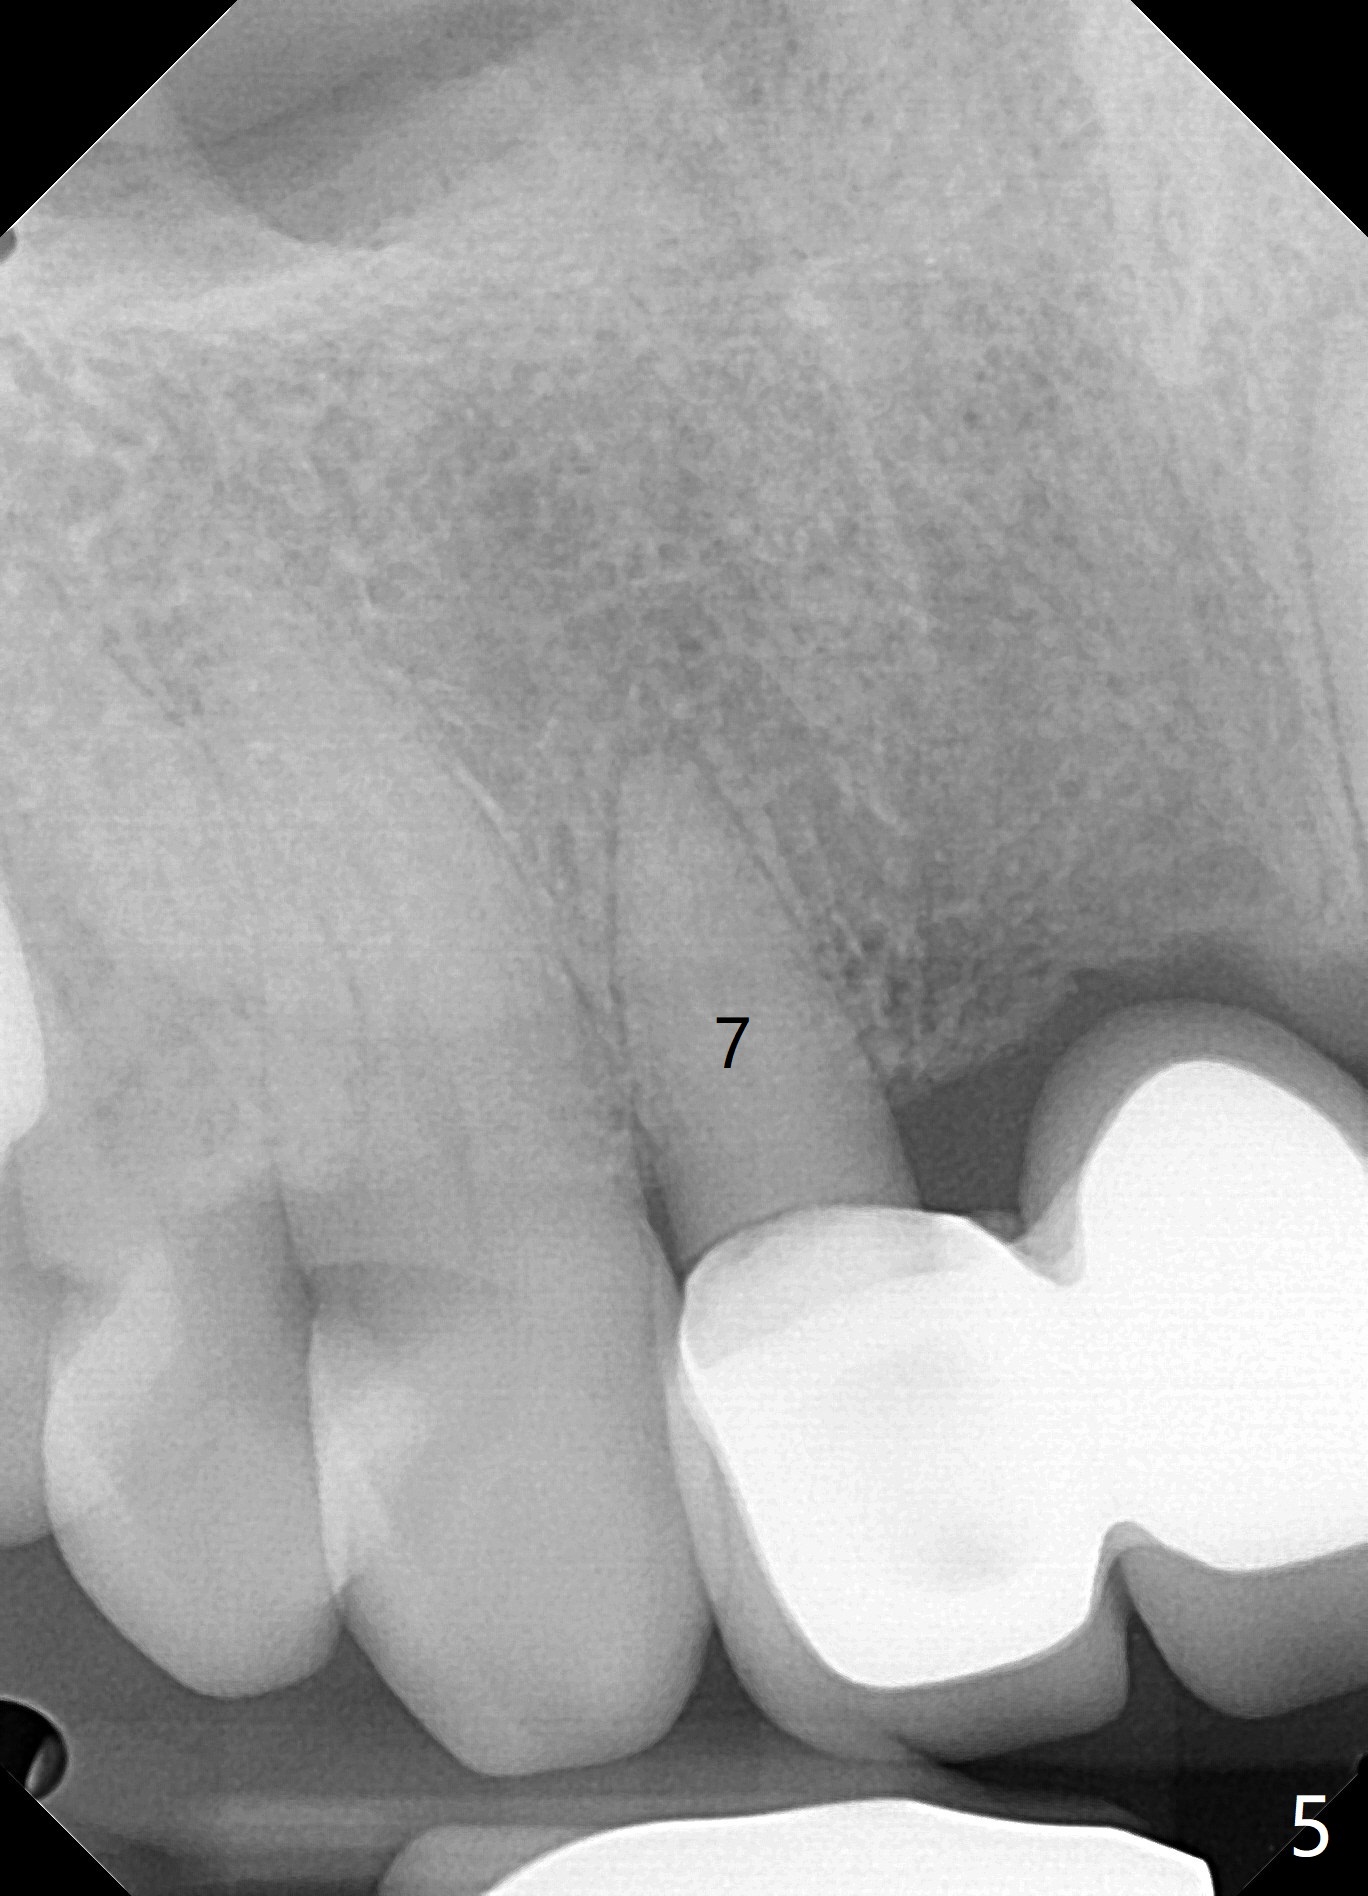

A 71 year old lady has issue with an upper bridge (#7-11, Fig.5-7). While one of the abutments (anchor teeth for FPD), #7, is "tender", the other (#11) fractures. Take Alginate impression (upper and lower) when she returns, pour models (no bubbles, 1 U, 2 L), and keep U Alginate for provisional. Section FPD at #7 and 9, take 12x9 cm CT with 2 cotton rolls and full arch impression for guide with bite registration. Prepare Endo Ice for #7 (tenderness). Tell the patient and her daughter that the lower left cantilever FPD is in bad shape, since the tooth #19 has large furca radiolucency (Fig.4 *). Next appointment should be scheduled for SRP (Fig.1-4).